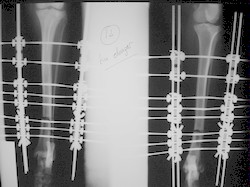

PRÁCTICAS CURSO DE FIJACIÓN EXTERNA PERFECCIONAMIENTO.

Elongacion.